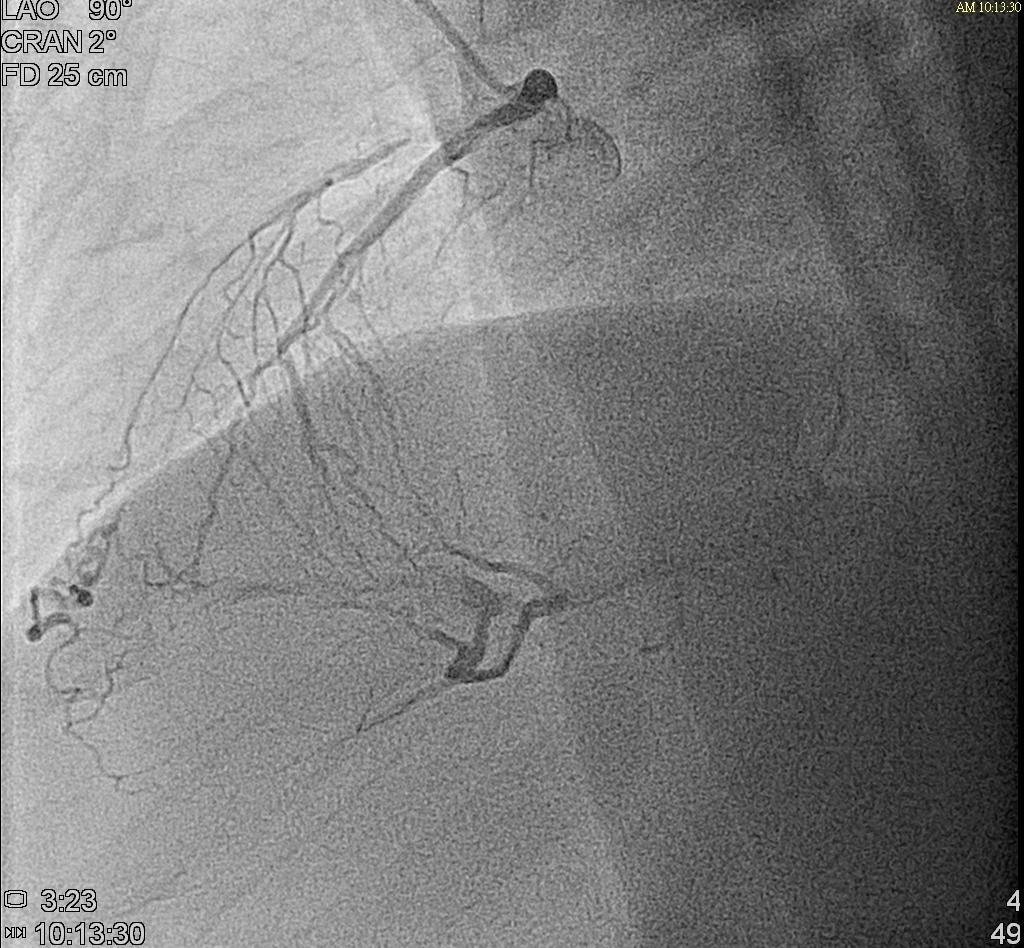

Right coronary artery: very large, long dominant RCA, supplying inferior and lateral wall, middle segment total occlusionWe referred him to cardiovascular surgeon for CABG evaluation but he refused and preferred PCI

Right coronary artery: very large, long dominant RCA, supplying inferior and lateral wall, middle segment total occlusionWe referred him to cardiovascular surgeon for CABG evaluation but he refused and preferred PCI

What is the optimal strategy revascularization for this patient? (1.CABG 2.PCI to left-main LAD lesion first then RCA ? 3.PCI to RCA lesion then left main-LAD ? Other options?)In 1st PCI procedure,we managed his RCA lesion first by antegrade approach.We used Miracle 6 guidewire and Conquest Pro guidewire.The microcatheter was successfully advanced into the lesion. The Fielder FC guidewire was then successfully navigated through the lesion.Dilatation with various sizes of PTCA balloon. 1.0x10mm, 2.5x15mm, 3.5x30mm).OptiCross IVUS showed vessel diameter ranging from 4.5 to 5mm over a length of 53mm. Two Synergy 4.0x38mm and 4.0x32mm drug-eluting stents (DES) were deployed at the middle to distal and proximal to middle RCA, respectively. Post-dilatated with 5.0x8mm NC Trek. The final IVUS confirmed excellent stent apposition and no residual stenosis.